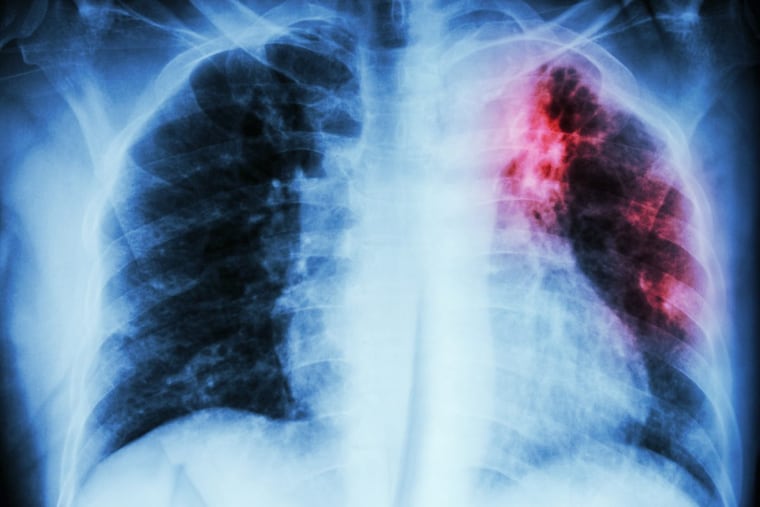

IPF causes scarring of the lungs, according to the report. It can be slowed, but nothing can remove the scar tissue. Over time, the lungs have difficulty getting oxygen to vital organs like the heart and brain.